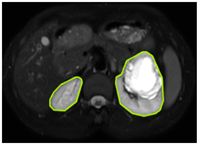

3.2.1. ROI Dataset

The images used in the study include different anatomical areas, such as the liver, spleen, and intestine. However, in order to process the data more quickly and provide more accurate results from the analysis, only the kidney areas (Regions of Interest, ROI) were extracted and evaluated. The Roboflow platform was used for spatial matching and segmentation of the kidneys. Polygonal ROI regions were defined by applying the semantic segmentation method, and then the transformations performed were verified by the radiologist, increasing the reliability of the system. In our study, MRI phase images were acquired at a resolution of 512 × 512 and the renal region of interest (ROI) was segmented and resized to 224 × 224 for input into the DenseNet architecture. In a similar study, Alhussaini et al. utilized 512 × 512 CT images and processed tumor-containing ROIs for their analysis; however, segmented region details were not provided [23]. Another study aimed to differentiate ccRCC from oncocytoma by extracting ROIs from T2-weighted images (T2-WI), pre-contrast T1-weighted images (T1-WI), and post-contrast arterial and venous phases. Tumor regions segmented at 100 × 100 mm were subsequently resized for input into the AlexNet model [24]. Unlike these studies, our approach involves segmenting the entire kidney, rather than solely the tumor region, to enable the deep learning model to leverage structural information for the organ as a whole.

Table 2 shows sample images containing ROI areas for different phases.

Table 2.

ROI areas in different phases.